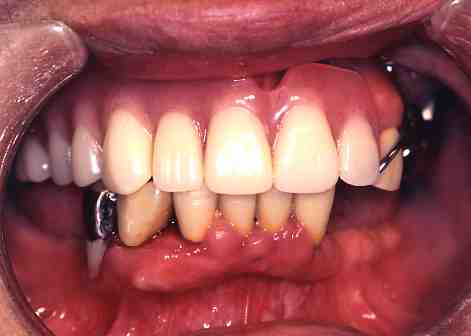

2.レーザー照射中